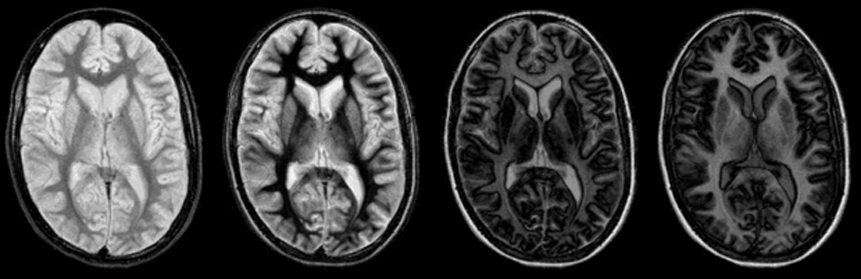

Figura 10-09:

The unexpected and abrupt contrast changes of an IR pulse sequence (cf. Figure 10-08): four images with increasing TI. One of the main problems (and advantages) of the IR sequence is that its con­trast be­ha­vi­or can change dramatically with only minimal changes of the inversion time.

Animation: In all images, TR = 4000 ms (different from the graph in Figure 10-08). TI from 100 ms to 2000 ms, increasing in steps of 100 ms.